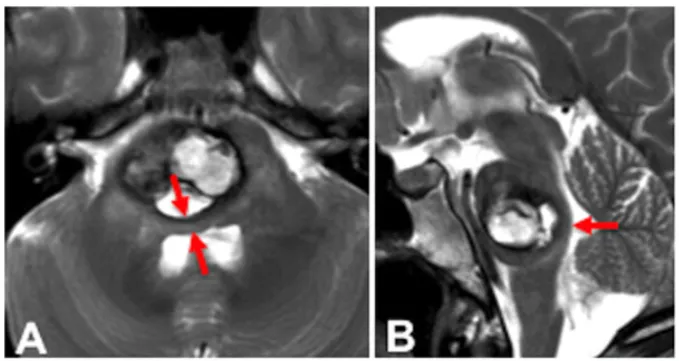

有没有药物可以先控制下 做不了手术,能不能放疗一下 脑干海绵状血管瘤手术风险大,可以选择放疗或者药物治疗吗?46岁女士突然感到左侧面部麻木。检查显示大出血性轴内桥脑海绵状血管...